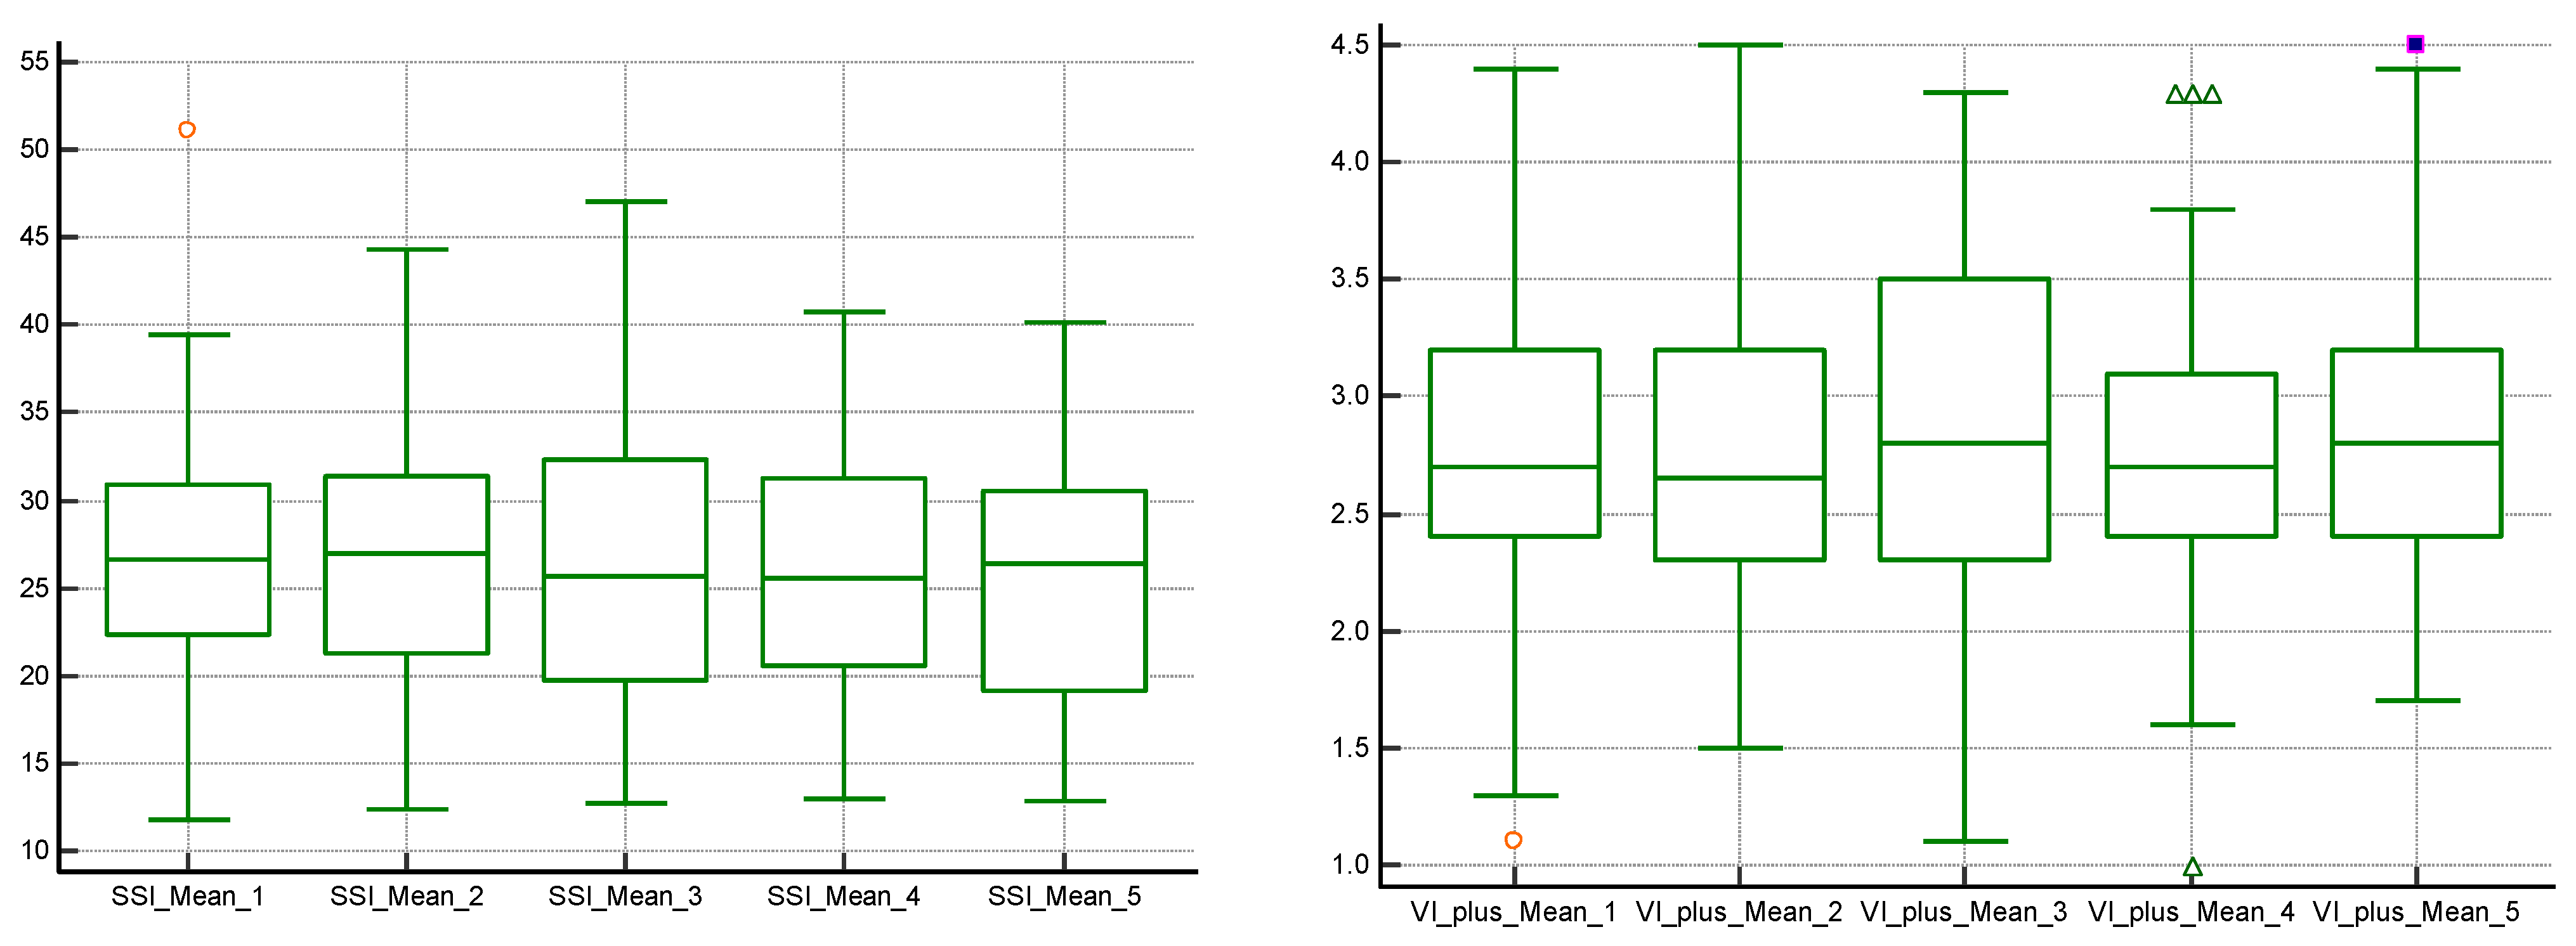

3. Results